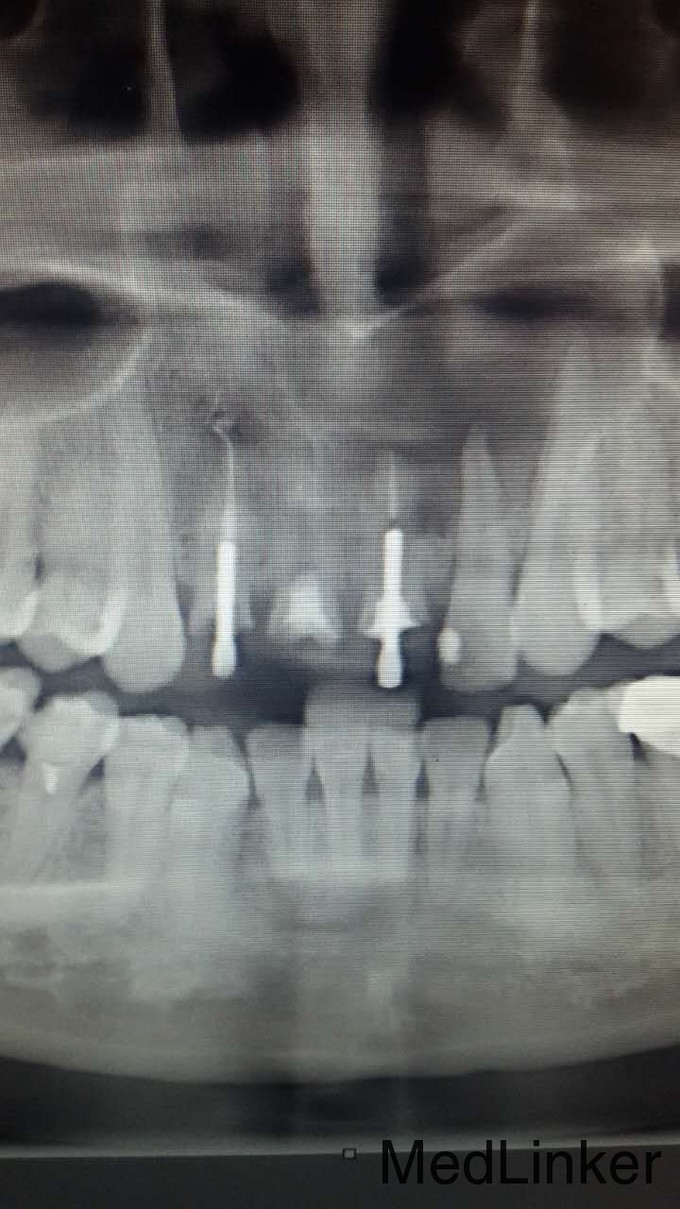

根管治疗桩核固定义齿修复

王婉君 女 29前牙残根要求固定义齿修复